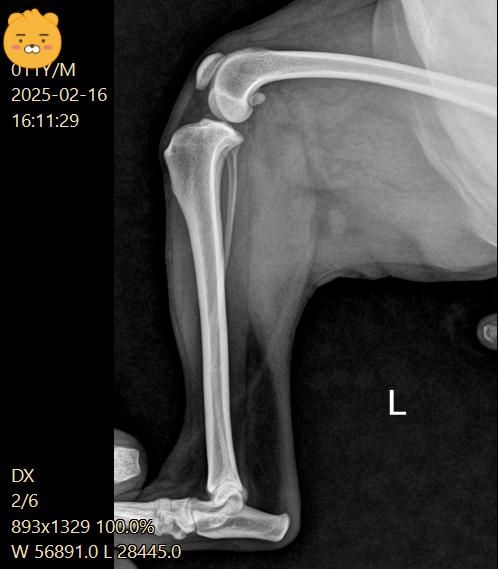

5일 간격으로 엑스레이를 찍었어요

5일후 진료는 십자인대는 애매하고 슬개골 2기로 수술 권유 받았어요

십자인대는 열어봐야 알 것 같다고 하셨고요

(첫번째 진료)

우측 관절낭이 좌측에 비해 종창 되어 관찰되고 경골 경사면 각도가 비교적 크게 관찰되어 십자인대에 손상이 있을 가능성이 있는 사진입니다. 이를 확인하기 위해서는 MRI 촬영이 필요하지만 현실적인 검사 방법은 아니라 추정일 뿐입니다. 하지만 방사선학적 관점에서 십자인대의 인장성 손상은 합리적인 추론입니다.